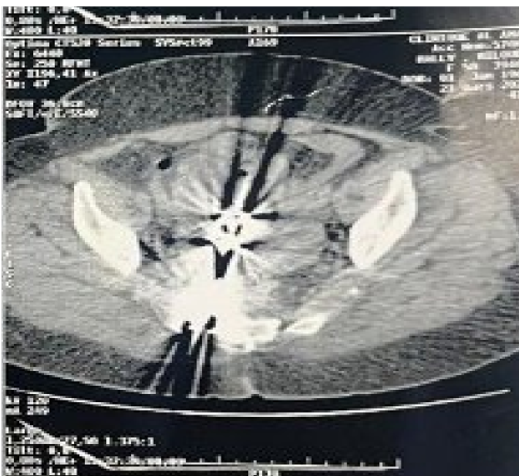

Intraoperative fluoroscopy identified two additional metallic fragments in pararectal positions. A visceral surgery team performed a Douglas pouch resection and dissection in an avascular presacral plane, allowing extraction of the remaining metallic fragments under radiological control. Postoperative course was uncomplicated.

Figure 4: Intraoperative fluoroscopy showing two metallic clamp fragments in the presacral space